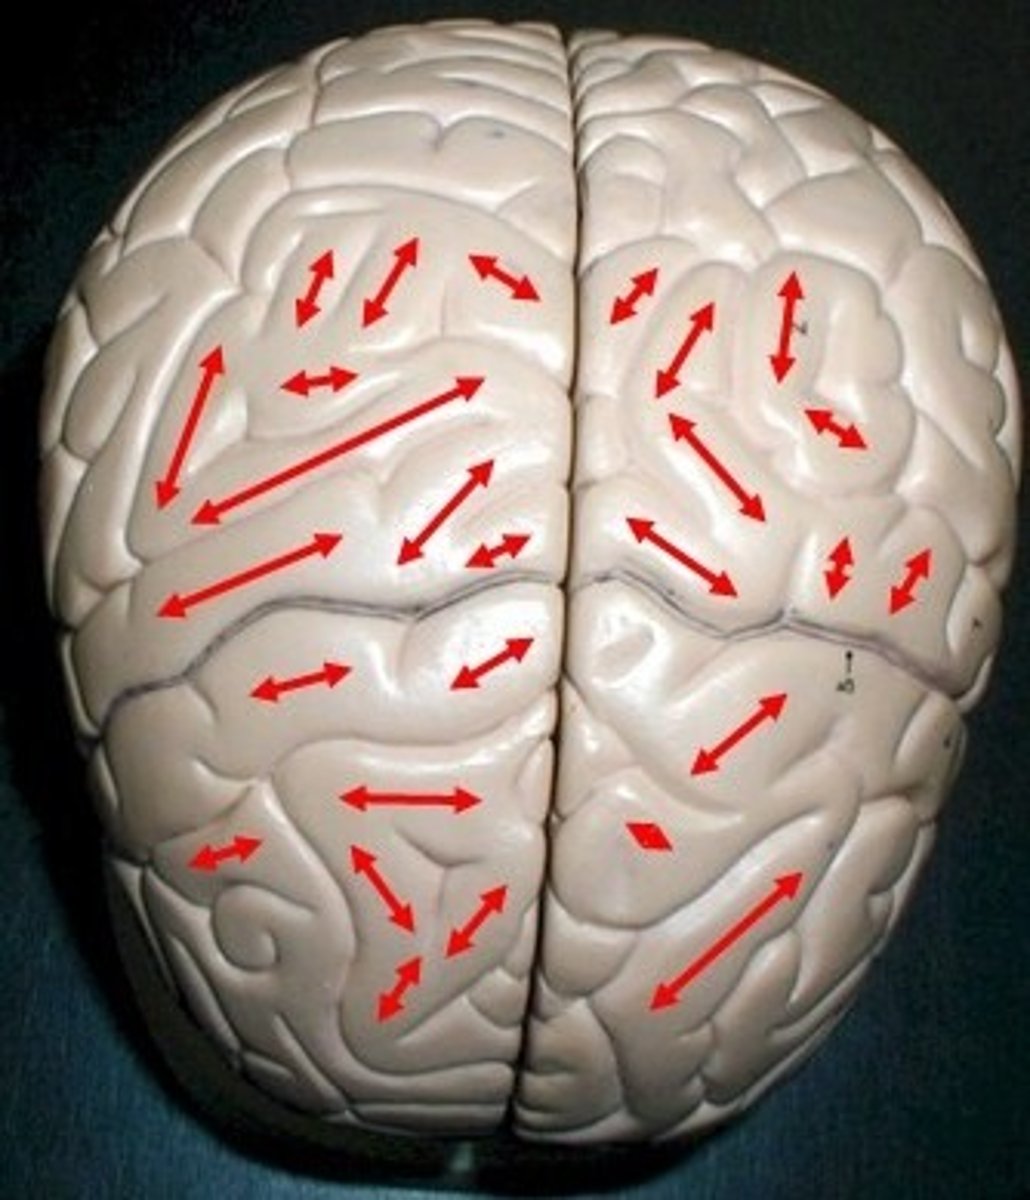

gyri